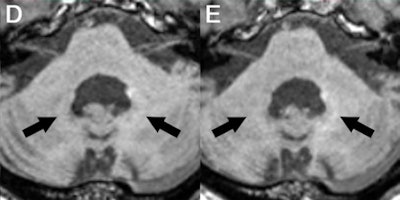

Axial MR images of a patient before (A) and after nine (B), 17 (C), 29 (D), and 41 (E) administrations of gadobutrol and gadoterate meglumine. Pre-existing hyperintensities in the dentate nucleus (most likely related to prior linear GBCA injection) are visible in all images. There is a slight decrease in hyperintensities between the baseline MRI and the MRI after 41 injections of macrocyclic GBCAs. Images courtesy of Radiology.